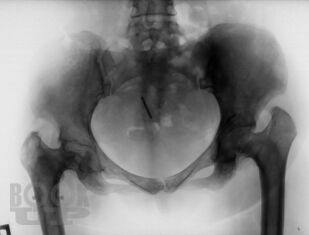

Болезнь Гоше относится к системным заболеваниям неопухолевой природы, в основе которых лежат наследственные дефекты метаболизма, приводящие к накоплению в органах и тканях нерасщепленных продуктов нормального обмена веществ. В случае болезни Гоше дефектом метаболизма является дефицит фермента, ответственного за метаболизм липидов.